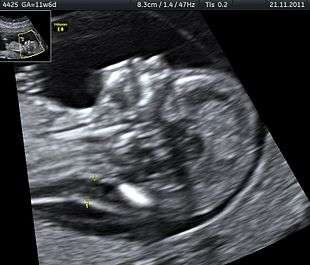

Ultrasound is often used to diagnose stillbirth and medical conditions that raise the risk

Often the cause is unknown.[1] Causes may include pregnancy complications such as preeclampsia and birth complications, problems with the placenta or umbilical cord, birth defects, infections such as malaria, and poor health in the mother.[2][4] Risk factors include a mother's age over 35, first pregnancy, smoking, drug use and use of assisted reproductive technology.[5] Stillbirth may be suspected when no fetal movement is felt. Confirmation is by ultrasound.[6]

It is unknown how much time is needed for a fetus to die. Fetal behavior is consistent and a change in the fetus' movements or sleep-wake cycles can indicate fetal distress.[18] A decrease or cessation in sensations of fetal activity may be an indication of fetal distress or death, though it is not entirely uncommon for a healthy fetus to exhibit such changes, particularly near the end of a pregnancy when there is considerably less space in the uterus than earlier in pregnancy for the fetus to move about. Still, medical examination, including a nonstress test, is recommended in the event of any type of any change in the strength or frequency of fetal movement, especially a complete cease; most midwives and obstetricians recommend the use of a kick chart to assist in detecting any changes. Fetal distress or death can be confirmed or ruled out via fetoscopy/doptone, ultrasound, and/or electronic fetal monitoring. If the fetus is alive but inactive, extra attention will be given to the placenta and umbilical cord during ultrasound examination to ensure that there is no compromise of oxygen and nutrient delivery.